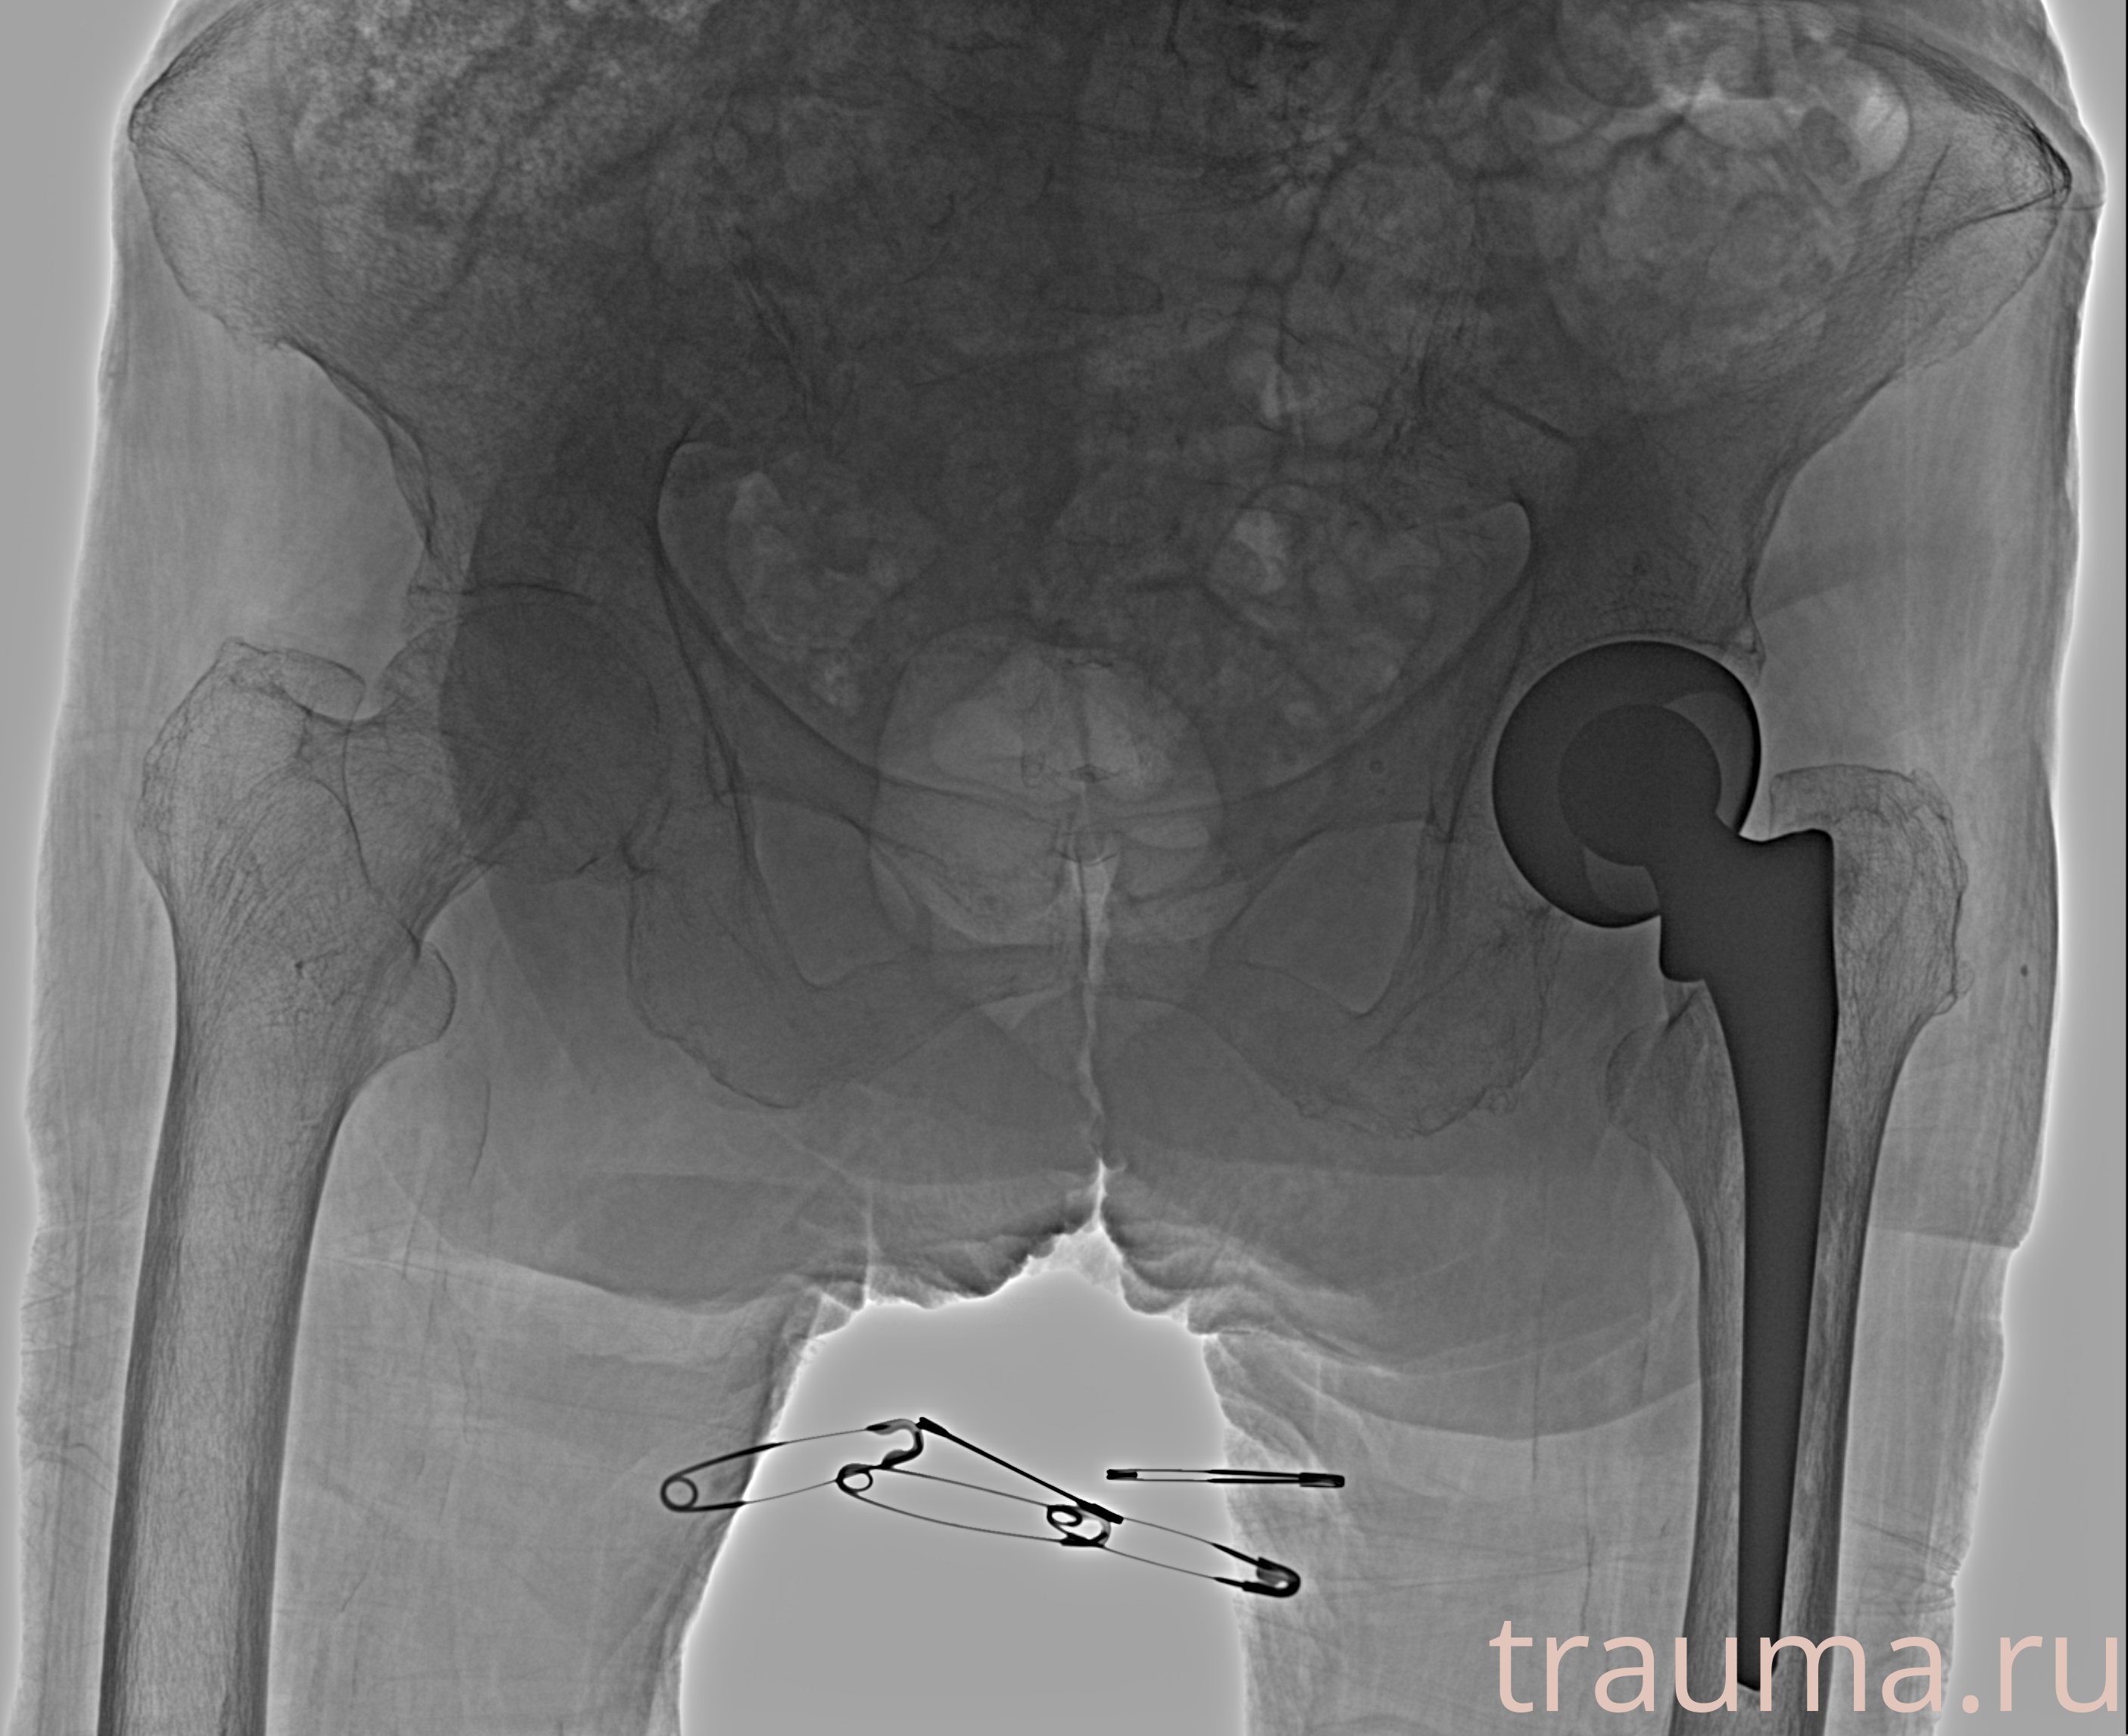

Рентгенограммы

Рентген на дому: по вашему адресу приезжает врач-рентгенолог, травматолог-ортопед с мобильным рентгеновским аппаратом, проводит диагностику травмы или заболевания, делает необходимые рентгенограммы, дает рекомендации по дальнейшему лечению. Получить качественные снимки в домашних условиях возможно благодаря уникальной методике, разработанной МосРентген Центром для института  Склифосовского